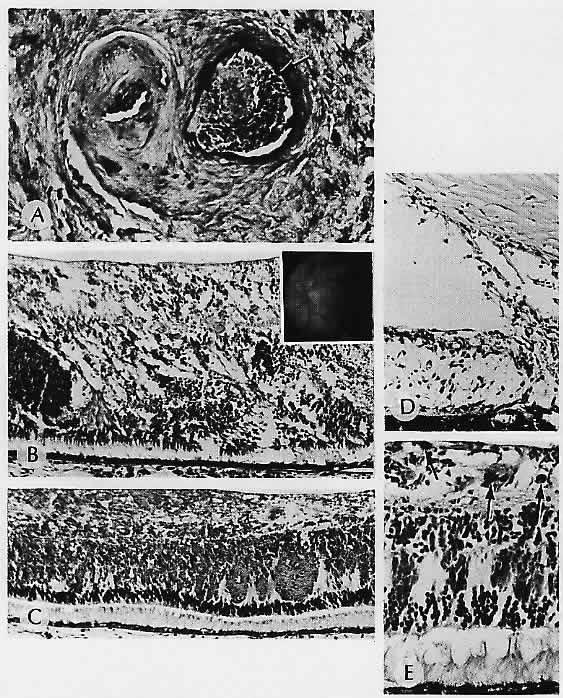

RETINAL HEMORRHAGIC INFARCTION (Fig. 8)

Fig. 8. Retinal hemorrhagic infarction. A. Central retinal vein is occluded and recanalized. The artery is identified by an internal elastic lamina (arrow). B. Hemorrhagic infarction causing disorganization of the retina in a patient with polycythemia vera and central retinal vein occlusion. Inset. Fundus following central retinal vein occlusion in an otherwise healthy 18-year-old girl; no cause for the occlusion was found. C. Sheets of blood in the inner retinal layers produce the characteristic fundus appearance. Note the preservation of the photoreceptors. D. Rubeosis iridis is present in the same patient with polycythemia vera. E. Pigment (arrows) is hemosiderin in a long-standing occlusion. (A, elastica, ×136; B, H&E, ×69; inset, fundus; C, H&E, ×69; D, H&E, × 101; E, Prussian blue, × 176)

In contrast to arterial occlusion, retinal vein occlusion is usually thrombotic and results in varying amounts of intraretinal hemorrhage. Central retinal vein occlusion can be divided into two types. The first type is nonischemic and is sometimes called venous stasis retinopathy39 (an unfortunate term, since ocular ischemia from diffuse hypoperfusion, discussed earlier, is also sometimes called venous stasis retinopathy). Nonischemic central vein occlusion is characterized by a variable number of flame-shaped and dot and blot hemorrhages but with few or no cotton-wool spots. As documented by fluorescein angiography, capillary perfusion is nearly normal, and thus the sequelae of ischemia, including iris neovascularization and neovascular glaucoma, are very rare in the nonischemic type. The visual prognosis is good.39

Ischemic central vein occlusion is also called hemorrhagic vein occlusion because of extensive retinal hemorrhage (the “blood and thunder” fundus). Numerous cotton-wool spots may be seen, but even if they are obscured by the hemorrhage, fluorescein angiography helps to document the extensive capillary closure and ischemia. Iris neovascularization is frequently associated and characteristically occurs between 6 weeks and 6 months (so-called 90-day glaucoma).39 With either type of vein occlusion, hemorrhage into the macula can result in permanent visual loss.

Histologically, central retinal vein occlusion appears acutely as hemorrhagic necrosis, with massive hemorrhage involving all layers of the retina (Fig. 9). The hemorrhage may also extend under the internal limiting membrane, separating it from the underlying nerve fiber layer. Cytoid bodies and optic nerve head edema may be present. Whether complete or “impending,” a thrombus occurs in the central vein,40although as Hayreh subsequently noted,39 only one of Green's cases was nonischemic histologically. All the rest had neovascularization of iris, optic disc, or both, sometimes with inner retinal ischemic atrophy.

Fig. 9. Hemorrhage within the nerve fiber layer (arrow) tends to “track” along the nerve fibers, producing a flame-shaped hemorrhage observed clinically. An accumulation of blood in the potential space between the internal limiting membrane (ilm) and the nerve fiber layer produces submembranous intraretinal hemorrhage, which is generally restrained from entering the vitreous compartment by the strength of the overlying thick basement membrane. Pockets of blood accumulating within the bipolar cell layer or between Henle's fibers (photoreceptor axons) of the extramacular outer plexiform layer produce the dot and blot hemorrhages seen clinically. (H&E, × 115)

Later in the evolution of the occlusion, exudates may occur in the outer plexiform layer. Other late changes include disruption, gliosis, and hemosiderosis of the retina. The retinal blood vessel walls can be markedly thickened. The thrombus is organized and may be recanalized.40